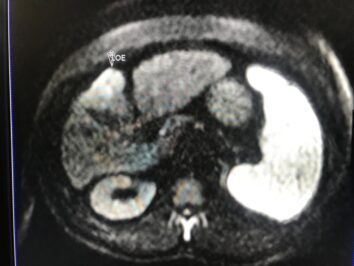

Masculino de 52 años, con cirrosis hepática. La elastografía ecográfica evidencia fibrosis Categoría F3 según escala de METAVIR y la presencia de múltiples nodulaciones, que en su mayoría son menores a 2 cm.

En este contexto, toda nodulación mayor de 1 cm, debe ser evaluada idealmente con RM trifásica con secuencia de Difusión , para discriminar si se trata de nódulos de regeneración , nódulos displásicos o hepatocarcinoma.

En el presente caso, encontramos una lesión típica de hepatocarcinoma en el segmento 5 ( hiperintensa en T2, restringe en la Difusión con ADC bajo. Realza heterogéneamente postcontraste EV, con wash out y presencia cápsula tardía).

El objetivo es identificar dentro de la multifocalidad de nódulos , un hepatocarcinoma precoz o de pequeño tamaño , cuando la posibilidad de tratamiento con intención curativa es viable , a pesar de la cirrosis.